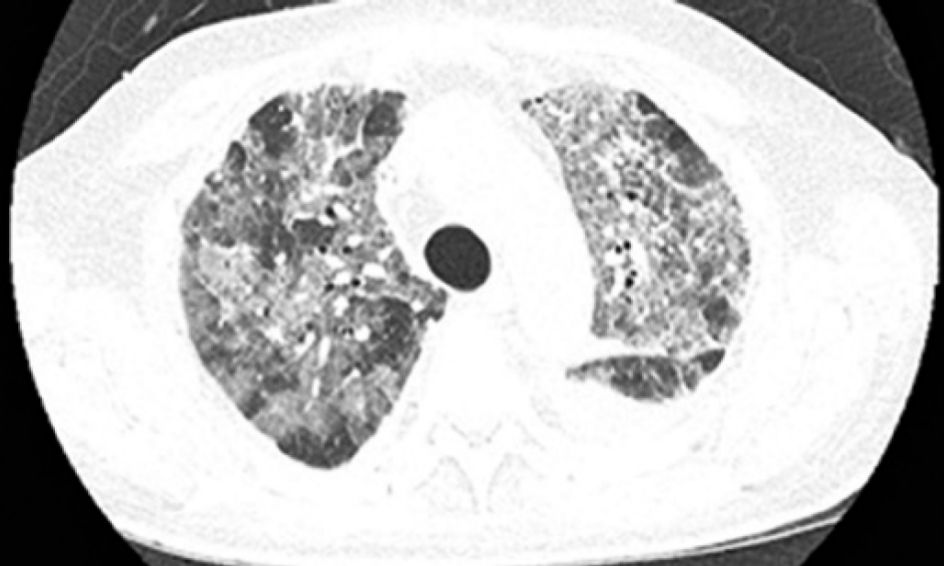

患者是一名69岁的老年男性,身患晚期转移性结肠癌,肿瘤已经转移到了肝、肺和骨组织。患者曾接受了氟嘧啶、铂、抗血管生成药、伊立替康和西妥昔单抗,但是不幸的是,所有治疗最终都没能改变病人的情况,肿瘤病情一直在持续不断的恶化,考虑到病人的实际情况,患者开始接受帕博利珠单抗(Pembrolizumabe)的治疗,每两周10mg/Kg,在第二次治疗之后,病人开始出现了发热和呼吸困难。体格检查显示,病人的血氧饱和度仅为83%,CT检查显示其左肺出现间质性肺炎,双侧胸腔都存在积液,血细胞计数显示病人的白细胞增多。为了控制肺部症状,患者在行胸腔穿刺术后,又使用了头孢曲松+克拉霉素,但是病情却并没有出现好转。CT复查显示病人的病情并没有因抗生素的使用而出现好转,反而进一步加重,双肺磨玻璃影进一步扩大。